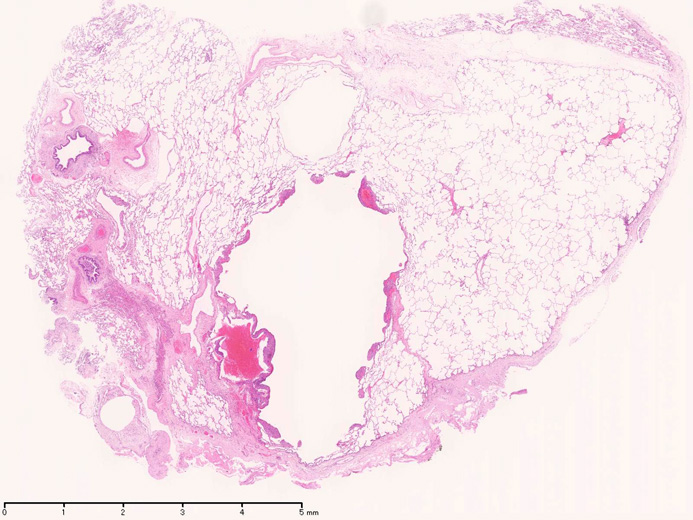

LAMの肺病変

嚢胞周囲または肺血管, リンパ管, 細気管支にそうLAM cellの浸潤, 集簇を特徴とする。LAM cellには2種類が認められ, 小型紡錘形細胞と細胞質の豊富な類上皮様細胞があり, 紡錘型は主に集簇巣の中心に存在し増殖能が高い。 類上皮様LAM cellは辺縁部に多く, 増殖能は低いがHMB45を強く発現している。

LAM cellの免疫染色--SMA, desmin, vimentin(vimentinはいつも陽性とはならない)が陽性となりmuscle lineageであるが典型的な筋細胞と異なり,

嚢胞形成はLAM cellの増殖と関連しており, 細胞が産生するmatrix metalloproteinases(MMPs)による組織破壊によるらしい。